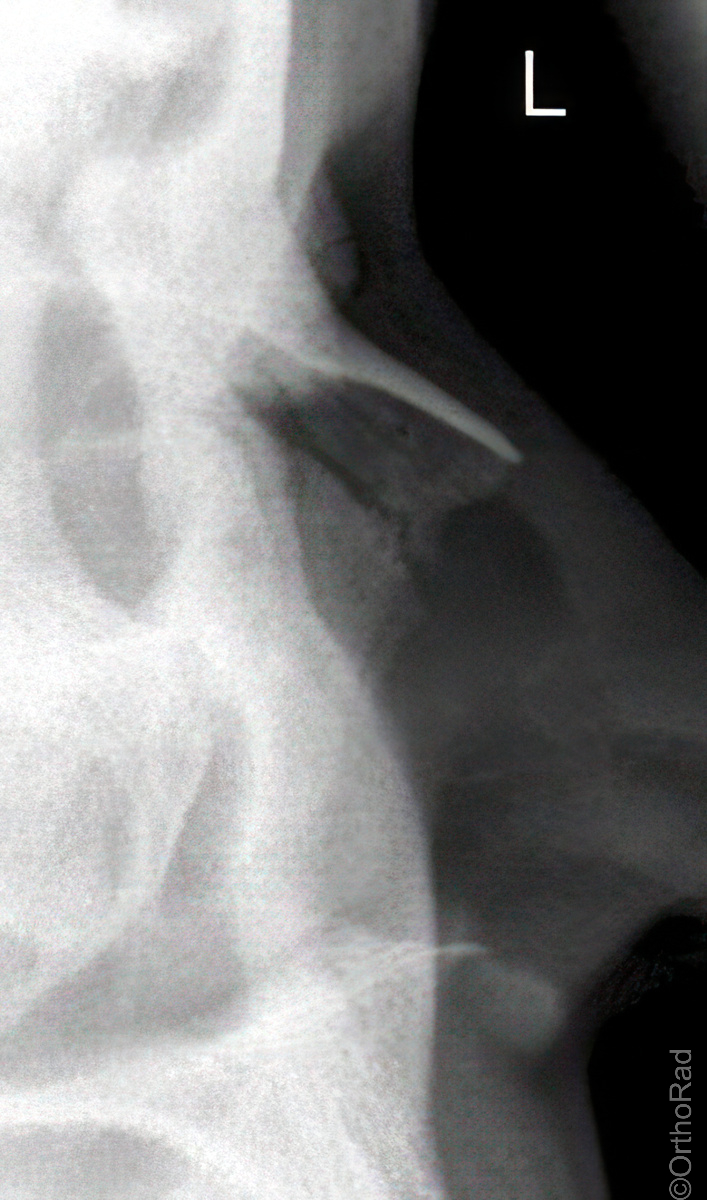

Felsenbein nach Schüller

Technik

• FDA: 1,15 m

• Ausgangsformat: 18/24

• mit Raster

• Röhrenkippung: 20° cranio-caudal

Lagerung

Patient in Bauchlage, d.h. stabile Seitenlage (Arm und Bein angewinkelt), wie Schädel seitlich, zu untersuchende Seite aufliegend, DH-Ebene senkrecht zum Bildempfänger. Ohr der aufliegenden Seite kann nach ventral umgeschlagen werden.

Zentralstrahl

zielt mit ca. 20° cranio-caudal auf das aufliegende Ohr. Zur Kontrolle: 3-4 Querfinger oberhalb der Ohröffnung. Querstrahl projiziert sich auf den Tragus vom aufliegendem Ohr.

Anmerkung

Mögliche Winkel belaufen sich zwischen 5° bis 35°. Immer beide Seiten aufnehmen.

Qualitätskriterien

Inneren und äußerer Gehörgang müssen sich kreisrund ineinander darstellen. Mastoidzellen sollten vollständig dargestellt werden.